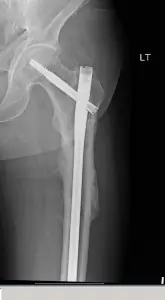

BGO's latest Comeback Champion story is from Waller "Scott" Mitchell. Mr. Mitchell had a fall this past June, and sustained a displaced subtrochanteric spiral hip fracture, which you can see in this first X-Ray. Essentially, Mr. Mitchell broke his femur, near his hip joint, and would unfortunately require surgery. Mr. Mitchell was seen at CHI-St. Joseph Main Hospital, and an emergency surgery was performed by BGO surgeon, Dr. Travis Hunt. Mr. Mitchell remembers, "It is strange when you have an emergency, and you do not know much about your surgeon. Thankfully, I now know I had a great doctor and feel confident to get back to 100% as he assured me would happen."